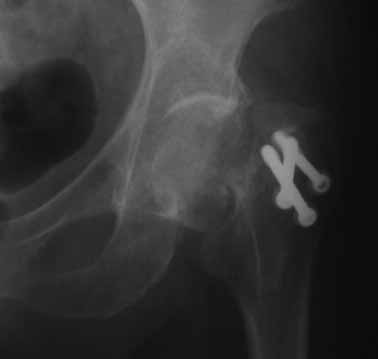

На консультации вот такие снимки. Больная 72 года. упала в быту 26 декабря 2010г.

Оперирована 30 декабря 2010г. в одном из стационаров края. Назначили дополнительное обследование, а пока хотелось-бы услышать мнение по-поводу возможностей сохранения головки. Больная из льготного контингента, т.е. современные констукции и эндопротез маловероятны.

Обычное после фиксации перелома шейки варусное смещение по разным публикациям встречается от 15-24%. В оценке состояния пожилых больных применяется коэффициент (ADL) Activities of daily living. В зависимости от базового ADL, т.е. до переломного состояния планируется лечение. Кроме того, возраст играет важную роль, и не всегда функциональное состояние совпадает с истинным возрастом. Поэтому каждый случай после 60 лет рассматривается отдельно.